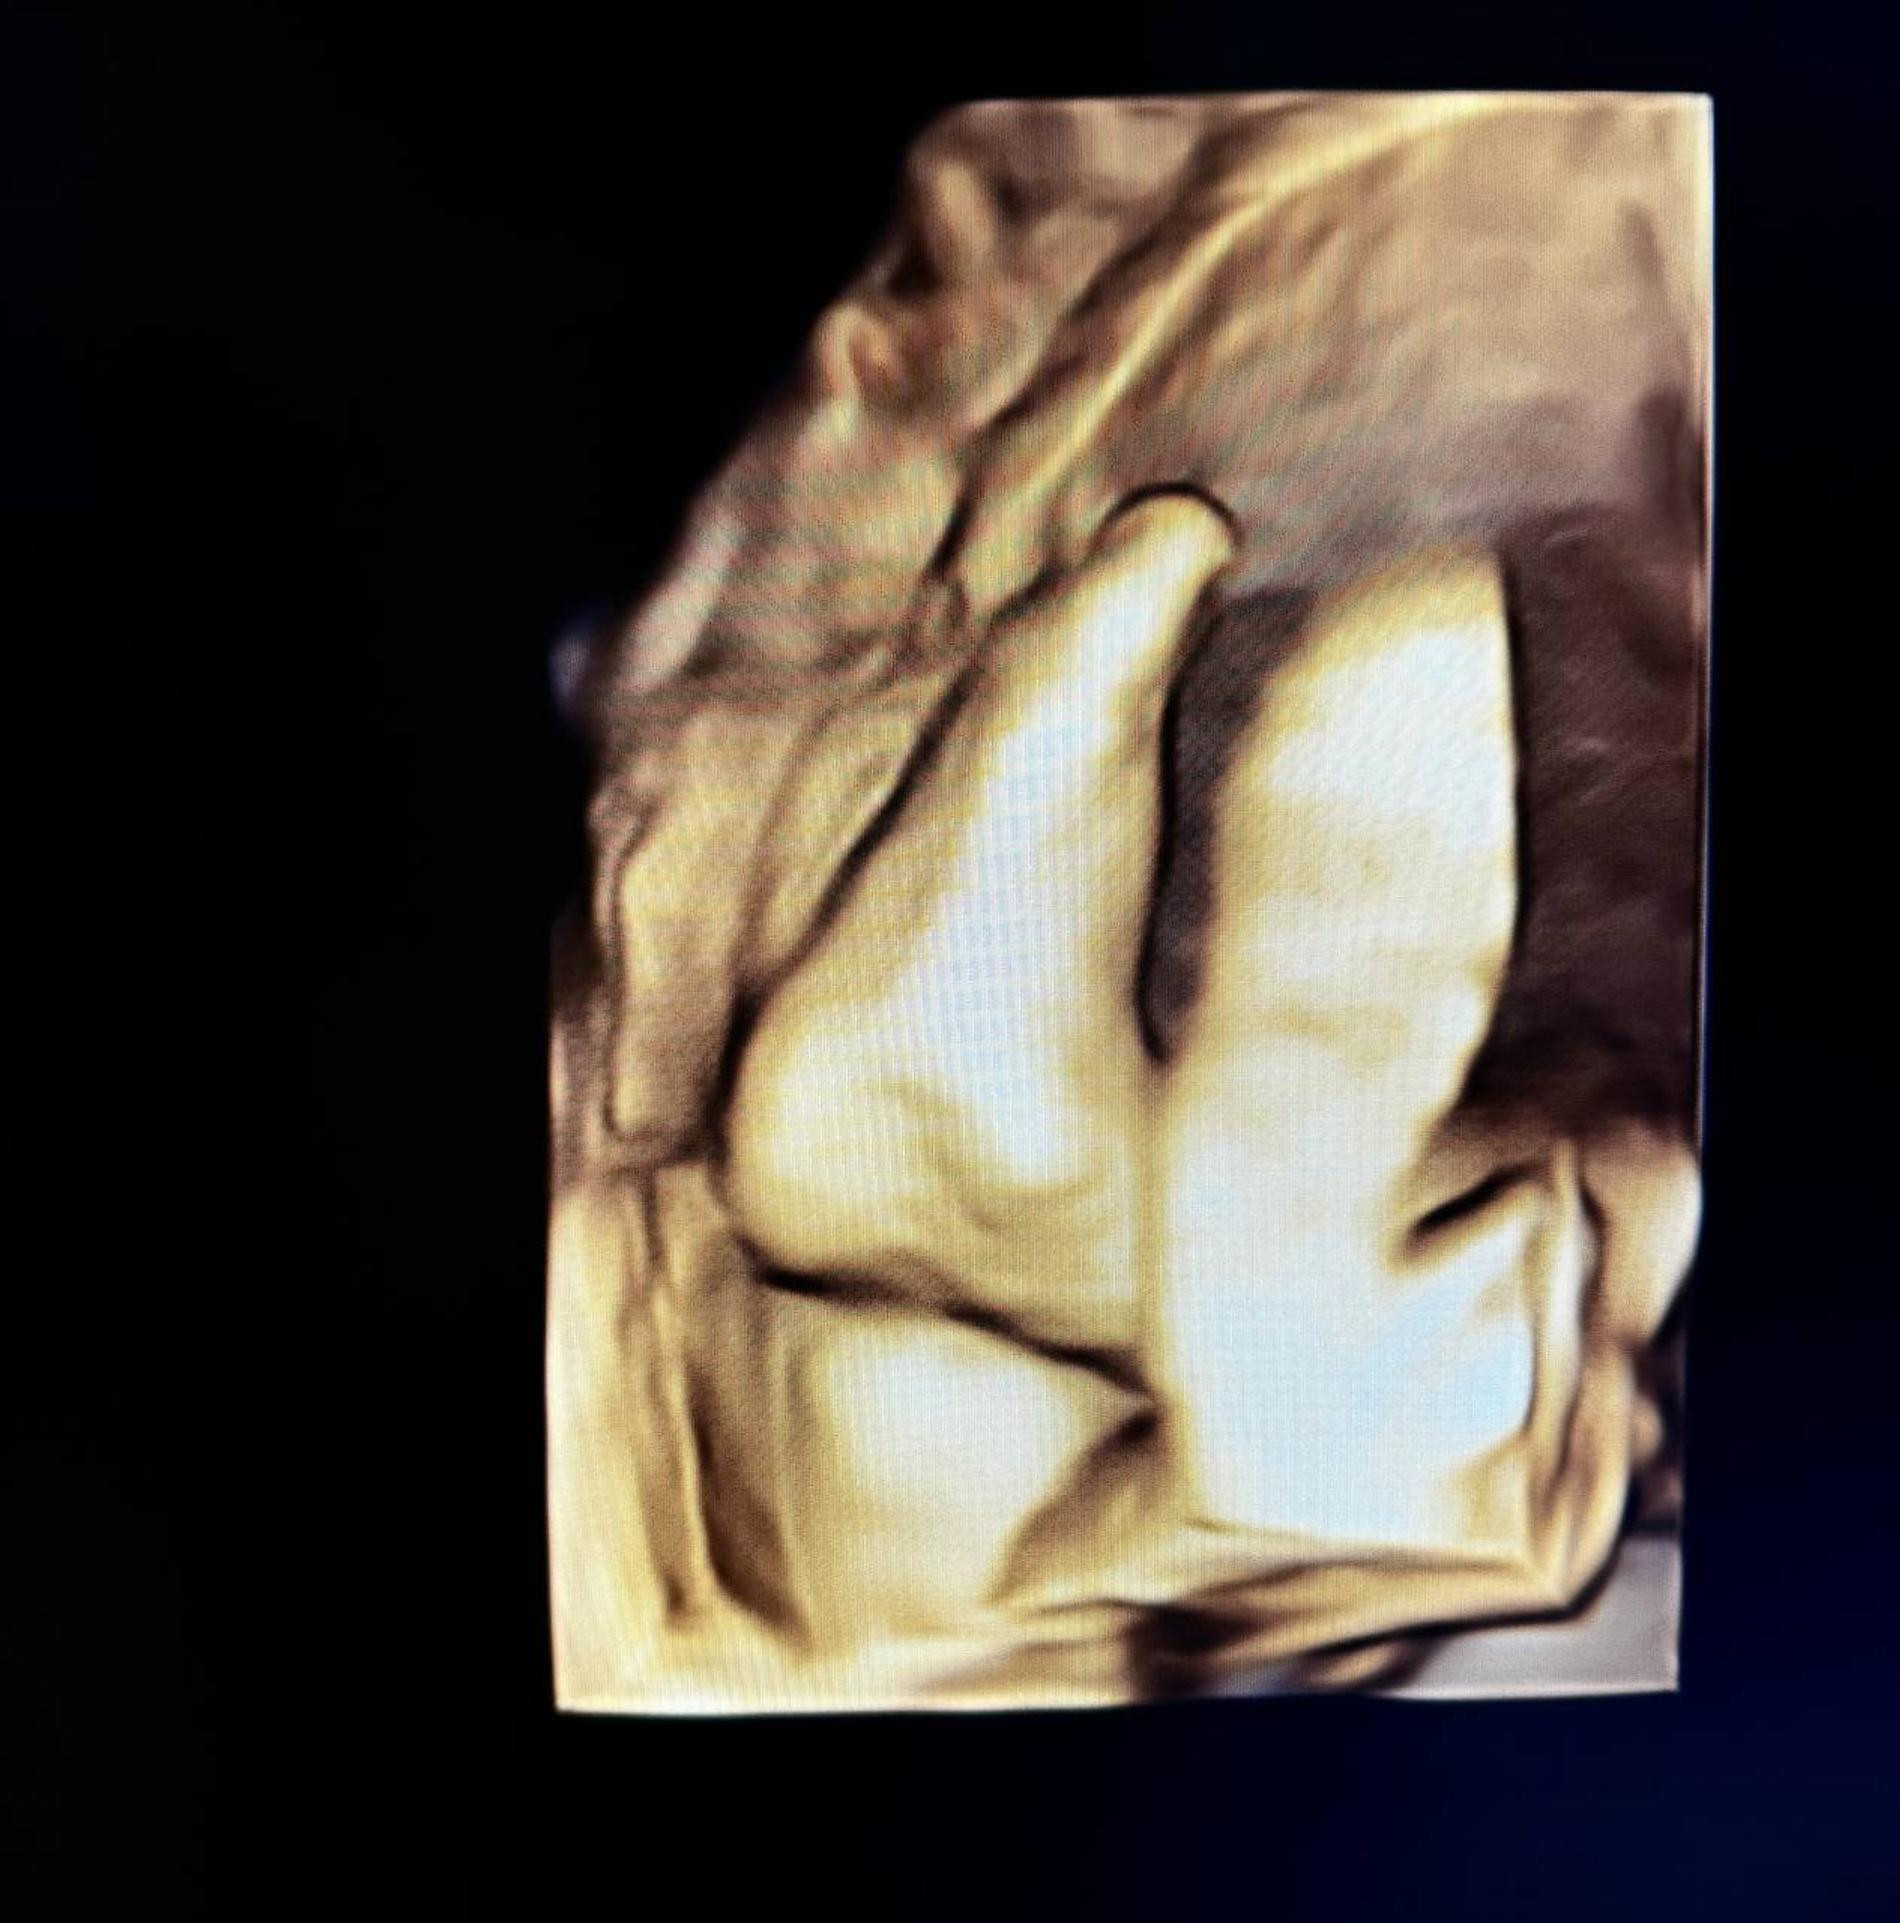

Фото Вашего Будущего Ребенка

Фото Вашего Будущего Ребенка 135 фото